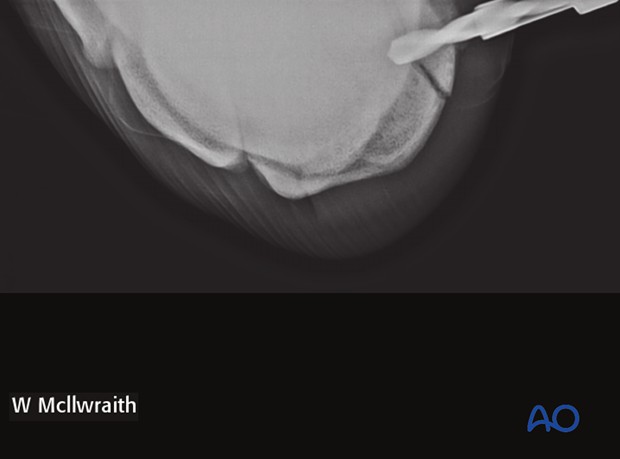

The drill depth and direction can be verified using an intraoperative radiographic view.

The 2.5 mm drill guide is inserted into the glide hole and a 2.5 mm hole is drilled through the third carpal bone just stopping short of the junction of the 3rd and 4th carpal bone (to a depth of about 40 mm).

The glide hole is lightly countersunk at the dorsal surface and debris flushed.

Correct screw length is determined using the depth gauge (screw length should be at least 4 mm shorter than the depth of hole). Generally a 36 mm long screw is used.

The hole is tapped with a 3.5 mm tap protected by the 3.5 mm drill guide. This should be done by hand.